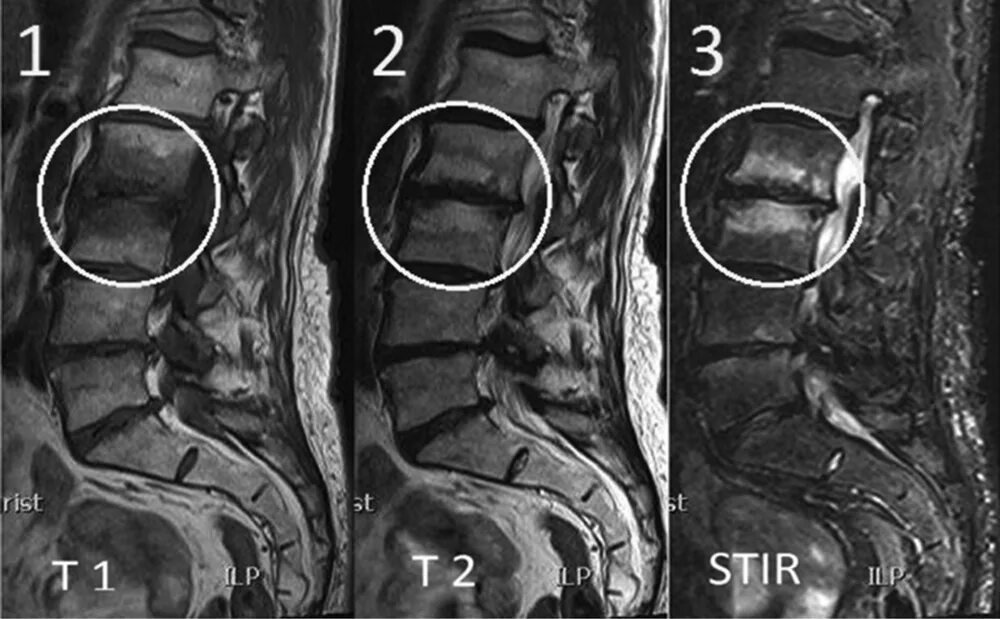

Изменение по типу modic 1